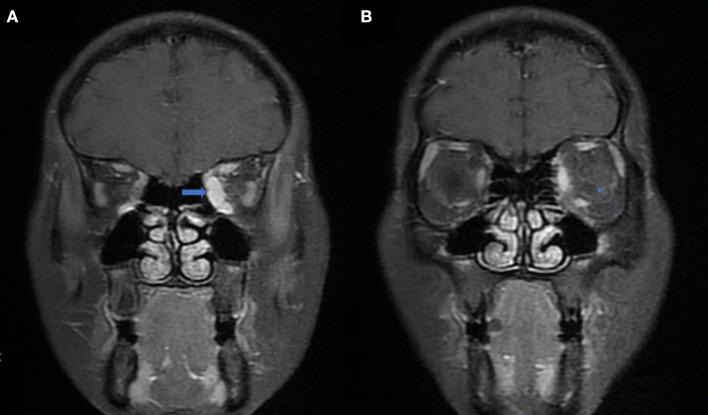

Optic perineuritis (OPN) is a special optic neuropathy that has a distinct etiology from neuromyelitis optica spectrum disorders (NMOSDs) or multiple sclerosis (MS)-related optic neuritis (ON). The mechanisms of how this inflammation developed and invaded the nerve sheath remain unknown. This study is aimed to analyze the etiology and different clinical characteristics of OPN in a Chinese patient population. Neuro-ophthalmological examination, orbit magnetic resonance imaging (MRI) and a series of blood samples were used in this retrospective observational cohort study to compare characteristics of OPN with idiopathic demyelination optic neuritis (IDON). Forty-four OPN cases (74 eyes) and 61 IDON cases (78 eyes) were analyzed. OPN cases included 33 cases (59 eyes) were associated with specific autoimmune diseases, 10 cases (13 eyes) were associated with infection diseases, 1 case was idiopathic disease. The causes of OPN with CTD were Graves' disease, Immunoglobulin G4-related disease (IgG-4 RD), granulomatosis with polyangiitis (GAP), systemic lupus erythematosus (SLE), Sarcoidosis, Rheumatoid arthritis, scleroderma, Behcet's disease, and gout. All patients received orbital MRI. Overall, 33 cases showed orbit fat infiltration. Specifically, nine cases with IgG-4 RD showed trigeminal nerve branch involvement, 12 cases with Graves' disease showed extraocular muscle belly enlargement, and 4 cases with GAP showed pterygopalatine fossa pseudotumor. Compared to IDON patients, OPN patients were older ( = 0.004) and more likely bilateral involvement 26 (78.79%) patients had bilateral involvement in OPN group vs. 17 (27.87%) in the IDON group ( < 0.001). Visual acuity scores using LogMAR testing was better in OPN patients compared to those with IDON, 0.55 ± 0.91 vs. 1.19 ± 1.24 ( < 0.001). Other ophthalmologic findings unique to the OPN group include 11 (33.33%) cases of ptosis, nine (27.27%) cases of diplopia, and 10 (30.30%) cases of exophthalmos, compared to zero cases of these conditions in the IDON group. Eight (13.11%) IDON patients also had multiple sclerosis (MS) and 7 (11.48%) patients had neuromyelitis which was significantly more than the zero patients in OPN group ( = 0.04). OPN had distinct etiologies and clinical characteristics from IDON and is more often associated with autoimmune diseases. Using OPN characteristics to diagnose autoimmune diseases should prove useful for clinicians when presented with patients that have multiorgan dysfunction that include ophthalmologic findings.

视神经周围炎(OPN)是一种特殊的视神经病变,其病因与视神经脊髓炎谱系障碍(NMOSD)或多发性硬化(MS)相关的视神经炎(ON)截然不同。这种炎症如何发展并侵犯神经鞘的机制尚不清楚。本研究旨在分析中国患者群体中OPN的病因及不同临床特征。在这项回顾性观察队列研究中,采用神经眼科检查、眼眶磁共振成像(MRI)和一系列血液样本,以比较OPN与特发性脱髓鞘性视神经炎(IDON)的特征。分析了44例OPN患者(74只眼)和61例IDON患者(78只眼)。OPN病例包括33例(59只眼)与特定自身免疫性疾病相关,10例(13只眼)与感染性疾病相关,1例为特发性疾病。与结缔组织病(CTD)相关的OPN病因包括格雷夫斯病、免疫球蛋白G4相关性疾病(IgG-4 RD)、肉芽肿性多血管炎(GAP)、系统性红斑狼疮(SLE)、结节病、类风湿关节炎、硬皮病、白塞病和痛风。所有患者均接受了眼眶MRI检查。总体而言,33例显示眼眶脂肪浸润。具体而言,9例IgG-4 RD患者显示三叉神经分支受累,12例格雷夫斯病患者显示眼外肌肌腹增大,4例GAP患者显示翼腭窝假瘤。与IDON患者相比,OPN患者年龄更大(P = 0.004),双侧受累的可能性更高,OPN组26例(78.79%)患者双侧受累,而IDON组为17例(27.87%)(P < 0.001)。使用LogMAR测试的视力评分在OPN患者中优于IDON患者,分别为0.55±0.91和1.19±1.24(P < 0.001)。OPN组特有的其他眼科表现包括11例(33.33%)上睑下垂、9例(27.27%)复视和10例(30.30%)眼球突出,而IDON组这些情况均为零例。8例(13.11%)IDON患者还患有多发性硬化(MS),7例(11.48%)患者患有视神经脊髓炎,这显著多于OPN组的零例患者(P = 0.04)。OPN与IDON有不同的病因和临床特征,且更常与自身免疫性疾病相关。当面对有多器官功能障碍并伴有眼科表现的患者时,利用OPN的特征来诊断自身免疫性疾病对临床医生应是有用的。